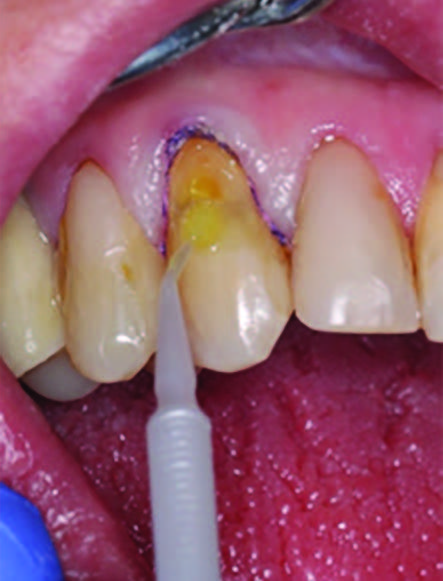

Figure 3. Application of caries indicator dye to identify the remaining infected tissue beneath the dislodged composite.

To improve isolation and soft tissue access, a retraction cord was placed before initiating the procedure (Fig. 2). The tooth was evaluated using a caries indicator dye (Kuraray Noritake Dental), helping to identify any remaining infected tissue beneath the dislodged composite (Fig. 3). Decay removal was completed with a diamond bur, and the enamel was bevelled using a starburst pattern to enhance aesthetic blending (Fig. 4). This preparation design was chosen for visual integration rather than bond strength enhancement.